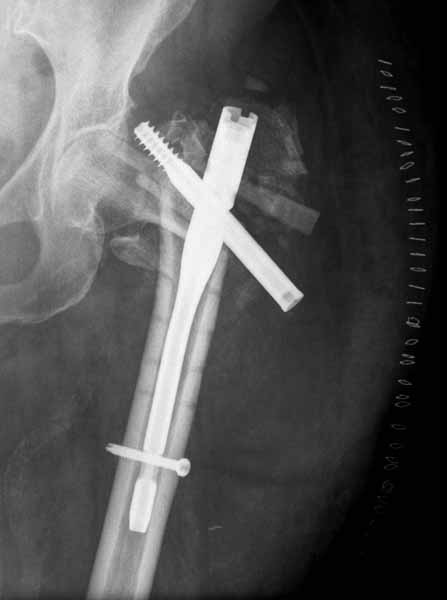

Банальный рутинный перелом чрезвертельной зоны лечимый DHS.

А по картинке можно сказать, что вроде бы все и неплохо. Предупредить миграцию шеечного винта при наружной ротации диафиза во время ходьбы достигают введением последнего поближе к переднему кортексу шейки. На Вашей картинке винт "смотрит" кзади. Отсутствие дополнительной боковой опоры для винта создает предпосылки для несостоятельности фиксации. (См. статью в прикреплении). Поэтому с ранней активизацией пациента в данном случае я бы подождал.

А пациент-то какой из себя?

При таком переломе мы бы тоже поставили вертельный гвоздь - на следующий день встать и побежать - чем не перспектива? На прямом снимке винт стоит замечательно, а коварный аксиальный подкачал, хотелось бы больше по центру шейки и головки завести. Да и смещение, какое-никакое, но есть. Посему - нагрузка 15 кг, а расширяли бы не раньше, чем через 5 недель.

Что касается данного перелома, то по-моему DHS или гамма - принципиальной разницы здесь конкретно нет - медиальная опора сохранена, при правильном исполнении можно ногу нагружать. Технически здесь выполнено на 3+, но если так же винт гаммы поставить - лучше не было бы.

Прилагаю снимок сделанный еще в стационаре через 2 недели после операции.

Кстати, я придерживаюсь мнения проводить шеечный шуруп через calcar - как самый прочный участок, сзади-снизу шейки. Есть мнения что лучше по центру - избежать эксцентрических сил и момента. По-моему трудно определить центр вращения (а может он уже определен) в плече бедра и шейке. Если calcar - это самое прочное место, то скорее всего это и есть центр нагрузки и ось вращения. Идея позиции перед передним кортексом - интересная, требует обдумывания.

Да, согласен, в такой же репозиции Гамма был бы таким же несостоятельным фиксатором. Проблема в репозиции медиального кортекса, который судя по снимку на месте и опора есть, а на самом деле не так. Как можно его проконтролировать? Дигитально, указательным пальцем пробраться через рану и пощупать? Иногда можно так репонировать перелом шурупом DHS - щупать пальцем язык перелома, который часто около малого вертела и можно до него достать пальцем и при малом разрезе, и поворачивая шуруп еще закручивая его на рукоятке репонировать перелом когда шуруп начнет брать кость. Если остеопороз не сильный и шуруп берет сразу, можно поставить антиротационный шуруп при репонированном положении перелома.

Проблема в репозиции медиального кортекса

При переломах типа A2 - с фрагментированием медиальной стенки - не получится ее репозиция никогда, что ж теперь, остеосинтез не делать?

Проблема основная тут в остаточном варусе. Даже если отломки по медиальной стенке при этом окажутся в контакте, от cutout это не спасет. Плюс короткий винт, еще и эксцентрично расположенный, так что совсем мало кости ему резать надо.

А так - чем более оскольчатый и дистально распространенный перелом, тем больше выбор склоняется к гвоздю. Но и он не спасет, если основные отломки оставить в варусе.

Добрый вечер! Гемипротез конечно же с цементной фиксацией ножки (вероятно Exeter). Видимо это прикол. перелом простой вертельный. фиксатор для перелома адекватный.репозиция хорошая и локализация винта в задневерхнем сегменте головки орпавдана по мнению многих коллег. Но "катаут" предусматривает не только прорезывание, но и ротационное смещение на фоне моновинтовой конструкции. Мы обязательно дополняем подубную конструкцию компрессирующим антиротационным винтом, опыт небольшой, но осложнений не имели. С уважением Ушаков СА.

Еще один технический момент, приводящий к вырезыванию DHS при вертельных переломах: недостаточно "глубокая" посадка винта.

Baumgaertner et al. The value of the tip-apex distance in predicting failure of fixation of peritrochanteric fracture fixation. J Bone Joint Surg Am. 1995;77-A:1058–1064 указывают, что расстояние от кончика винта до верхушки головки бедренной кости (Tip-apex Distance)должно быть менее 25 мм, в противном случае вероятность "cut out" повышается.

расстояние от кончика винта до верхушки головки бедренной кости (Tip-apex Distance)должно быть менее 25 мм

Во-1-х, 25 мм - по одной проекции это сильно далеко, так что TAD - это сумма этих расстояний по прямой и боковой проекциям.

Во-2-х, tip (этот самый кончик винта) может располагаться на одинаковом расстоянии от apex, но по разные стороны от него. См. исходную картинку из статьи Баумгартнера (c одной проекцией), а на другой - вот это самое по обе стороны. Самоочевидно, который из двух вариантов введения ближе к cut-out, несмотря на одинаковое расстояние от apex.

Первые снимки показывают технические погрешности установки DHS. Не была достигнута репозиция, конечность в флексии и шейка в ротации. Сегодня все меньше обращают внимание на параметры для оценки репозиции (S контуры Lowell в обеих проекциях и Garden Alignment Index, в норме 155 и 180 градусов), хотя такие простые тесты помогли бы дорепонировать смещение. Винт находится сзади в головке, что при нагрузке поменяет вектор и вместо компрессии в линии перелома срежет головку-Cut Out!

В зависимости от дистанции линии перелома и латерального кортекса надо использовать разной длины barrel, т.е. конец баррели не должен доходить до пределов перелома. Здесь конец длинного ствола упирается в медиальный фрагмент, что мешает созданию компрессии, а более короткий barrel создал бы запас для компрессии. В боковой пластине вместо 4х можно было ограничится двумя шурупами, потому что головка шурупа в 4.5 мм выдерживает давление до 350 кг.

Вторая операция- это фаза сохранения головки бедра. Желательно приложить все усилия и сохранить головку, но, как видно, “фиаско” продолжается. Здесь вместо нейтрализации сил между медиальной и латеральными сторонами была попытка удержать варус. Варус не удержать ни деротационными шурупами о котором говорили и не костными стружками вбитые в шейку, потому что вся нагрузка упирается в головку.